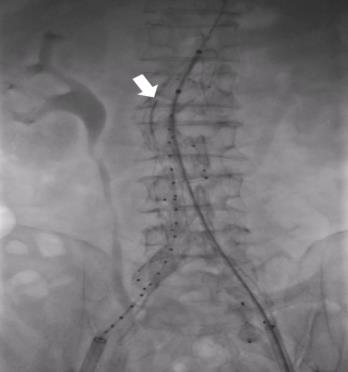

图6 判断瘤腔填充是否完全 A:回缩主动脉阻断球囊后,造影剂不流动;B:经导管动脉测压;C:存在内漏时,瘤腔内压力检测到动脉波形;D:内漏消失后,瘤腔内压力波形为一直线;E:内漏消失后,预置导管无反流血Fig.6 Assessment of complete aneurysm sac filling A: No contrast flow after withdrawal of the aortic occlusion balloon; B: Intra-arterial pressure measurement via catheter; C: Presence of an arterial waveform within the sac pressure tracing when an endoleak exists; D: A flat pressure waveform within the sac after resolution of the endoleak; E: Absence of blood reflux from the pre-positioned catheter after elimination of the endoleak